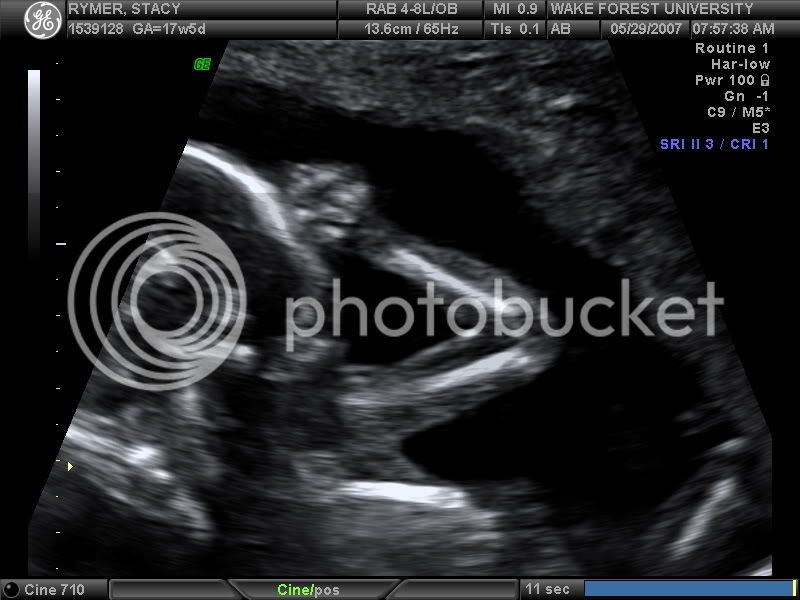

Fantastic!! Congrats to both of you! But to Stacy...you are da woman! I hope I can do it with no drugs too!

j/k she is a trooper and I'm very proud of her.